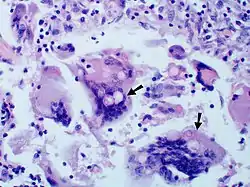

Once suspected, the diagnosis of blastomycosis can usually be confirmed by demonstration of the characteristic broad based budding organisms in sputum or tissues by KOH prep, cytology, or histology.[16] Tissue biopsy of skin or other organs may be required in order to diagnose extra-pulmonary disease. Blastomycosis is histologically associated with granulomatous nodules. Commercially available urine antigen testing appears to be quite sensitive in suggesting the diagnosis in cases where the organism is not readily detected. While culture of the organism remains the definitive diagnostic standard, its slow growing nature can lead to delays in treatment of up to several weeks. However, sometimes blood and sputum cultures may not detect blastomycosis.[17]

Large yeast-like fungi seen within giant cells at arrows.

Large yeast-like fungi seen within giant cells at arrows.Budding yeasts in cytoplasm of giant cells at arrows. Broad-based budding and double contoured cell wall seen in the giant cell in the center is characteristic of Blastomyces dermatitidis.